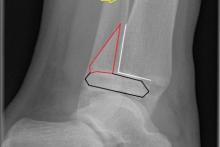

Rozpoznanie: W badaniu RTG - złuszczenie nasady dalszej kości piszczelowej lewej (czarne linie), z oderwaniem klinowatego fragmentu kostnego (czerwone linie) od tylnej części przynasady (białe linie). Złamanie kości strzałkowej (żółta strzałka).